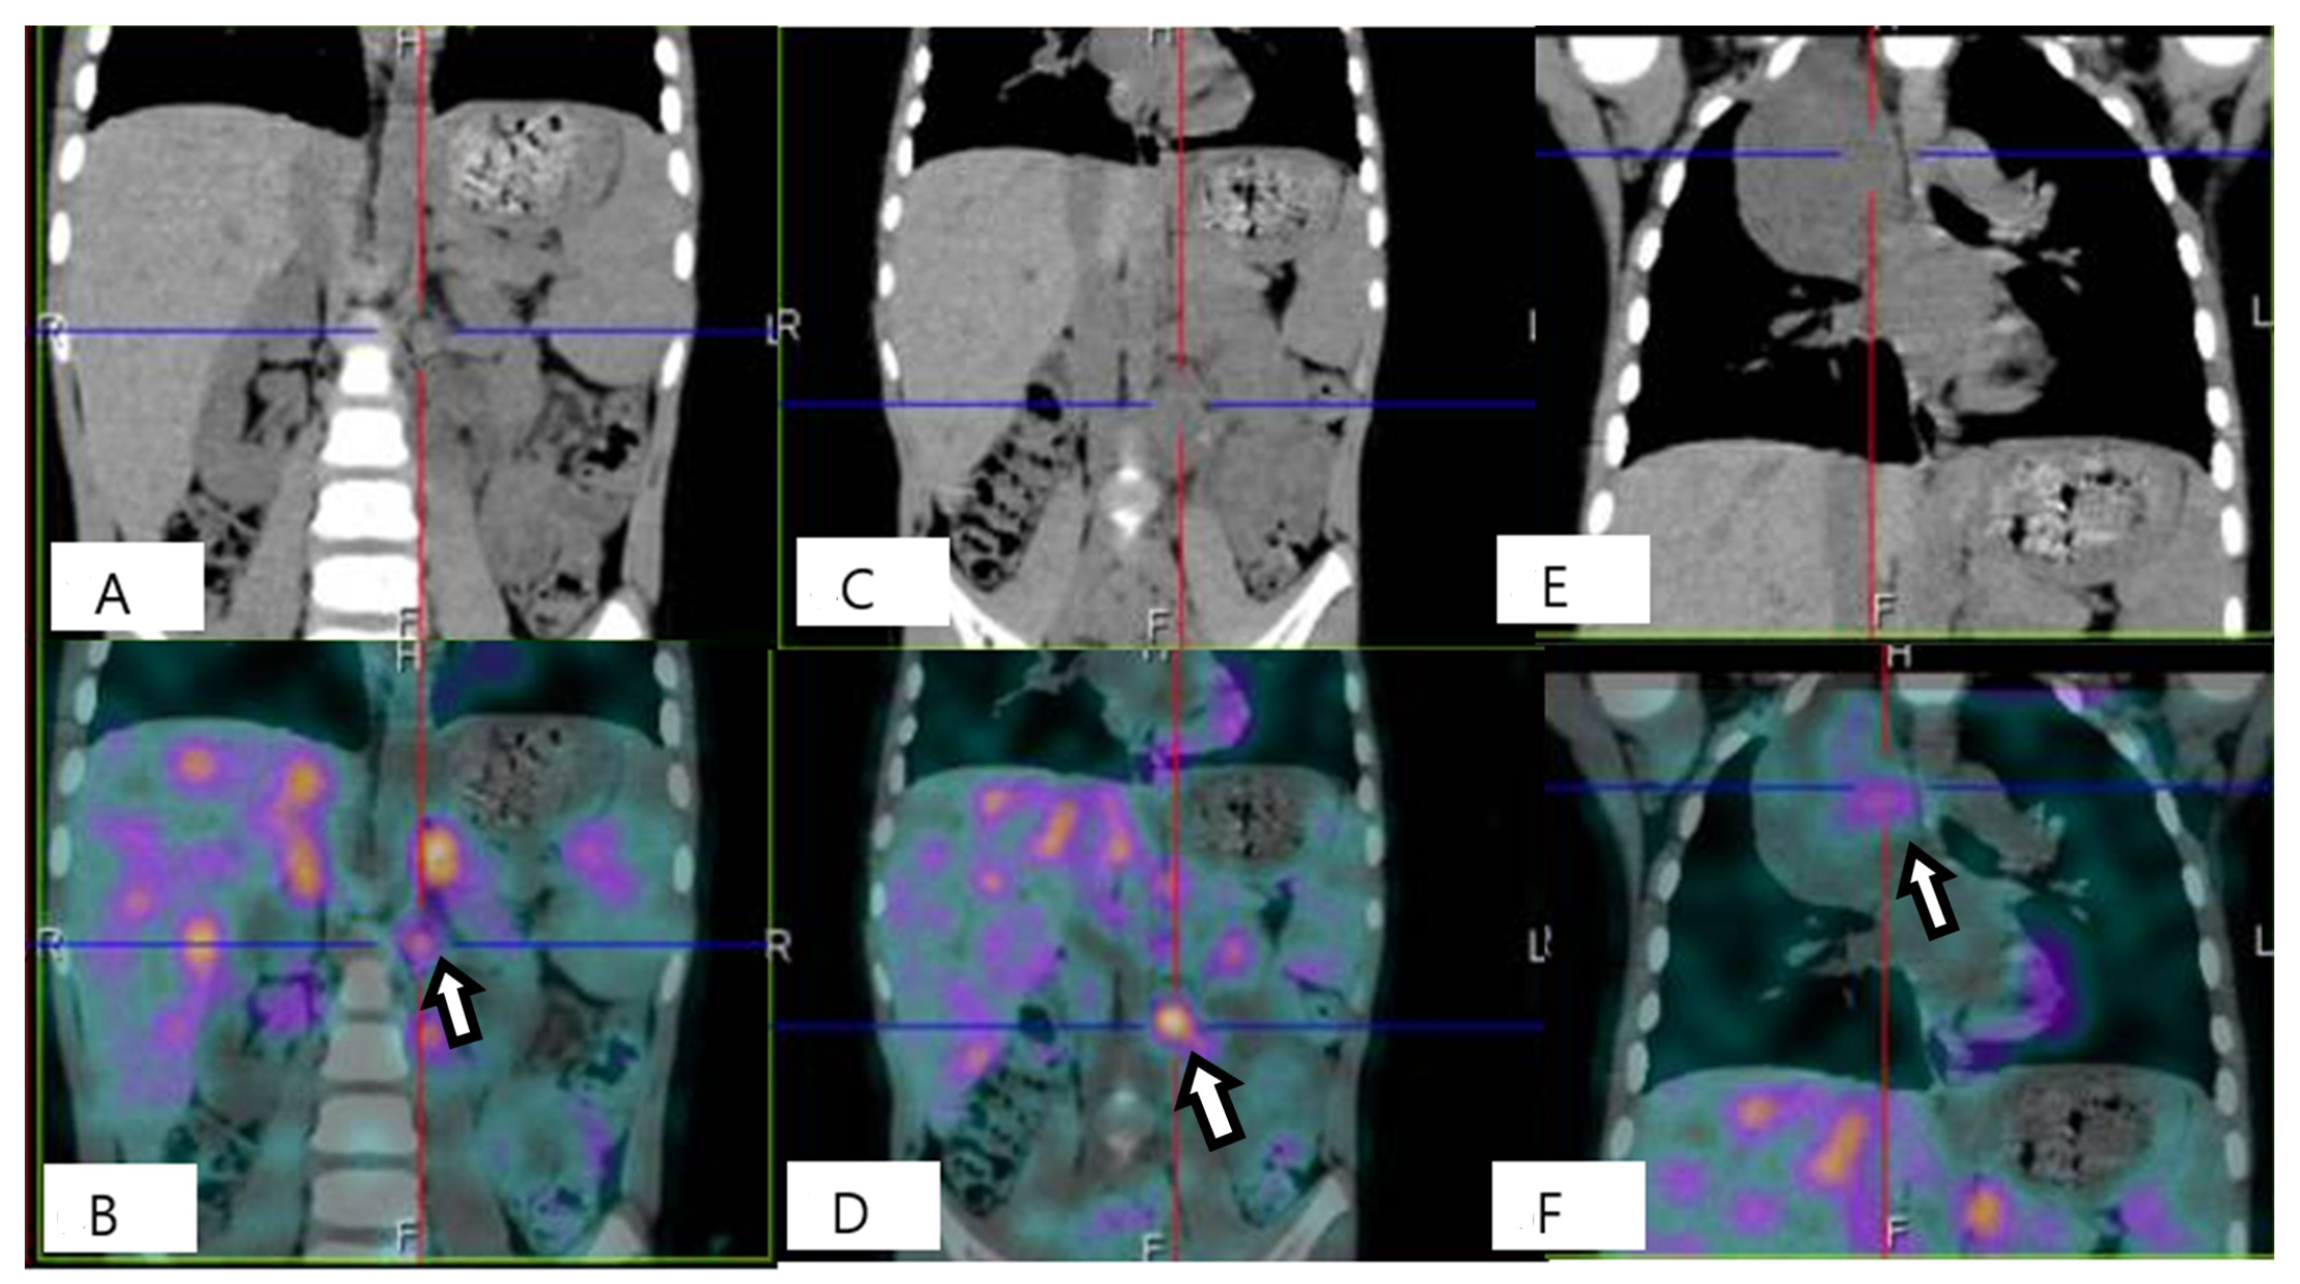

Figure 3. Scintigraphy with 123I- meta-iodobenzylguanidine (123I-MIBG) scan at baseline. To stage the tumor, a 123I-MIBG scan was performed, showing diffuse slight uptake in the thoracic mass (A,B) and an inhomogeneous uptake pattern in the abdominal mass (C,D) without metastatic lesions. A bone marrow aspiration was performed to complete staging and showed no evidence of neuroblastic cells. Based on the radiological features and according to the INRG Staging System (INRGSS), the mediastinal and abdominal lesions were defined as an L2 stage [2]. In view of the GNBI diagnosis (a low-risk tumor), the critical location of the neoplasms and the total absence of clinically evident symptoms, a watch-and-wait strategy was chosen [1,3].